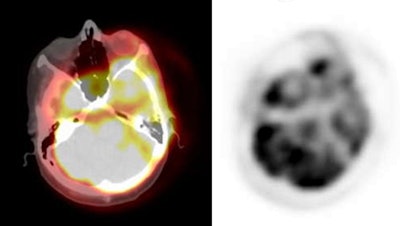

| Attenuation correction: The images below are from the same patient. The image on the left is non-attenuation corrected (the lungs and skin surface appear warm). The right image is corrected for attenuation. Note the improved visualization of structures deep within the body. |